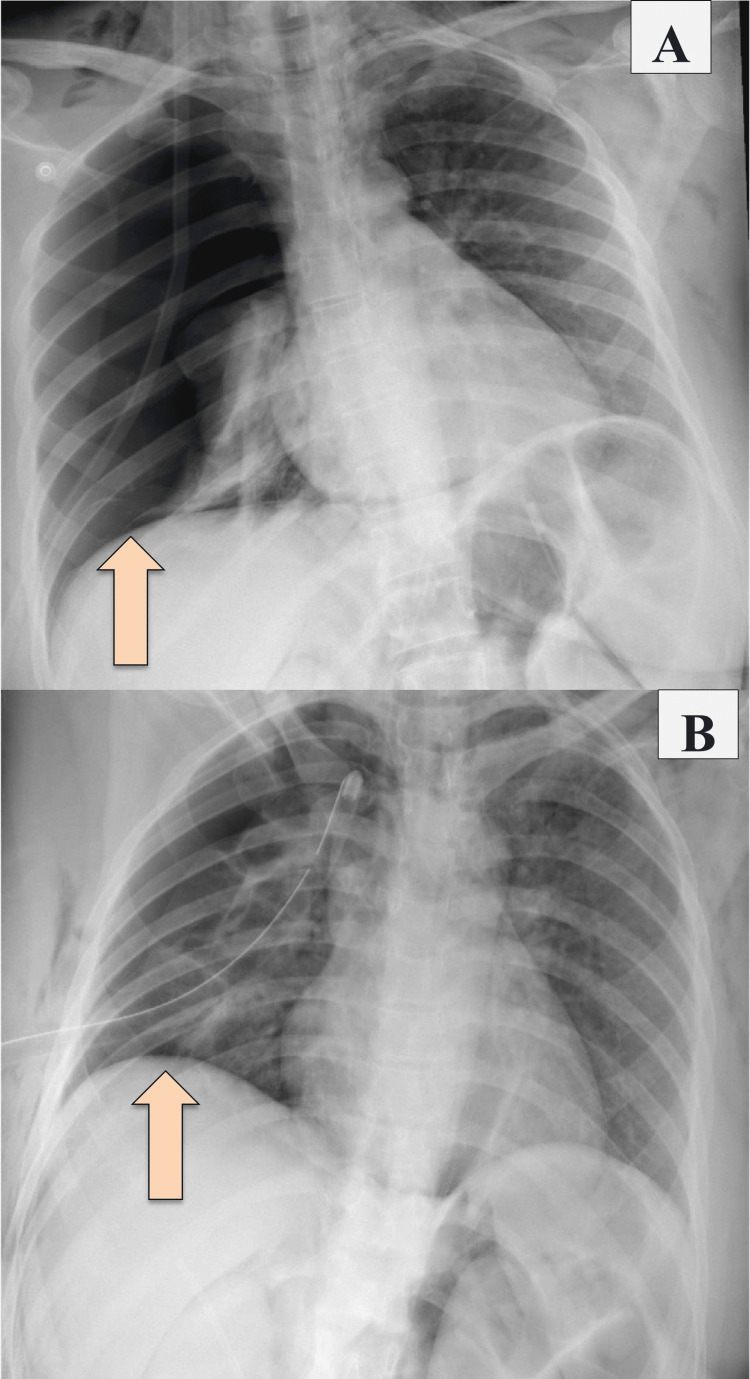

A nasogastric tube (NGT) was inserted and kept on free drainage (no bilious content was seen). She was kept NPO on IV fluid, serial abdominal examinations were done, and the patient was planned for CT abdomen with IV and oral contrast. A chest X-ray was done and showed right-sided pneumothorax and pneumomediastinum, and for that, a chest tube was inserted (Figure 1).

CT abdomen with IV and oral contrast post-ERCP showed pneumobilia with evidence of stent in the biliary system seen in a satisfactory position, significant pneumoretroperitoneam, small amount of retroperitoneal leaked contrast inferior to the second part of the duodenum, bulky and edematous pancreatic head, and uncinate process suggestive of acute pancreatitis, no intra-abdominal collection, and minimal amount of free fluids. There was extensive soft tissue emphysema along the anterior neck, lateral chest, and abdominal wall, severe pneumomediastinum, and minimal bilateral pneumothoraxes, with a chest tube seen on the right side in a satisfactory position, and a tiny area of contrast leakage was seen in the right posterior-lateral of the mid esophagus at T6 (Figures 2–4). The impression was double perforation at the second part of the duodenum and esophagus.